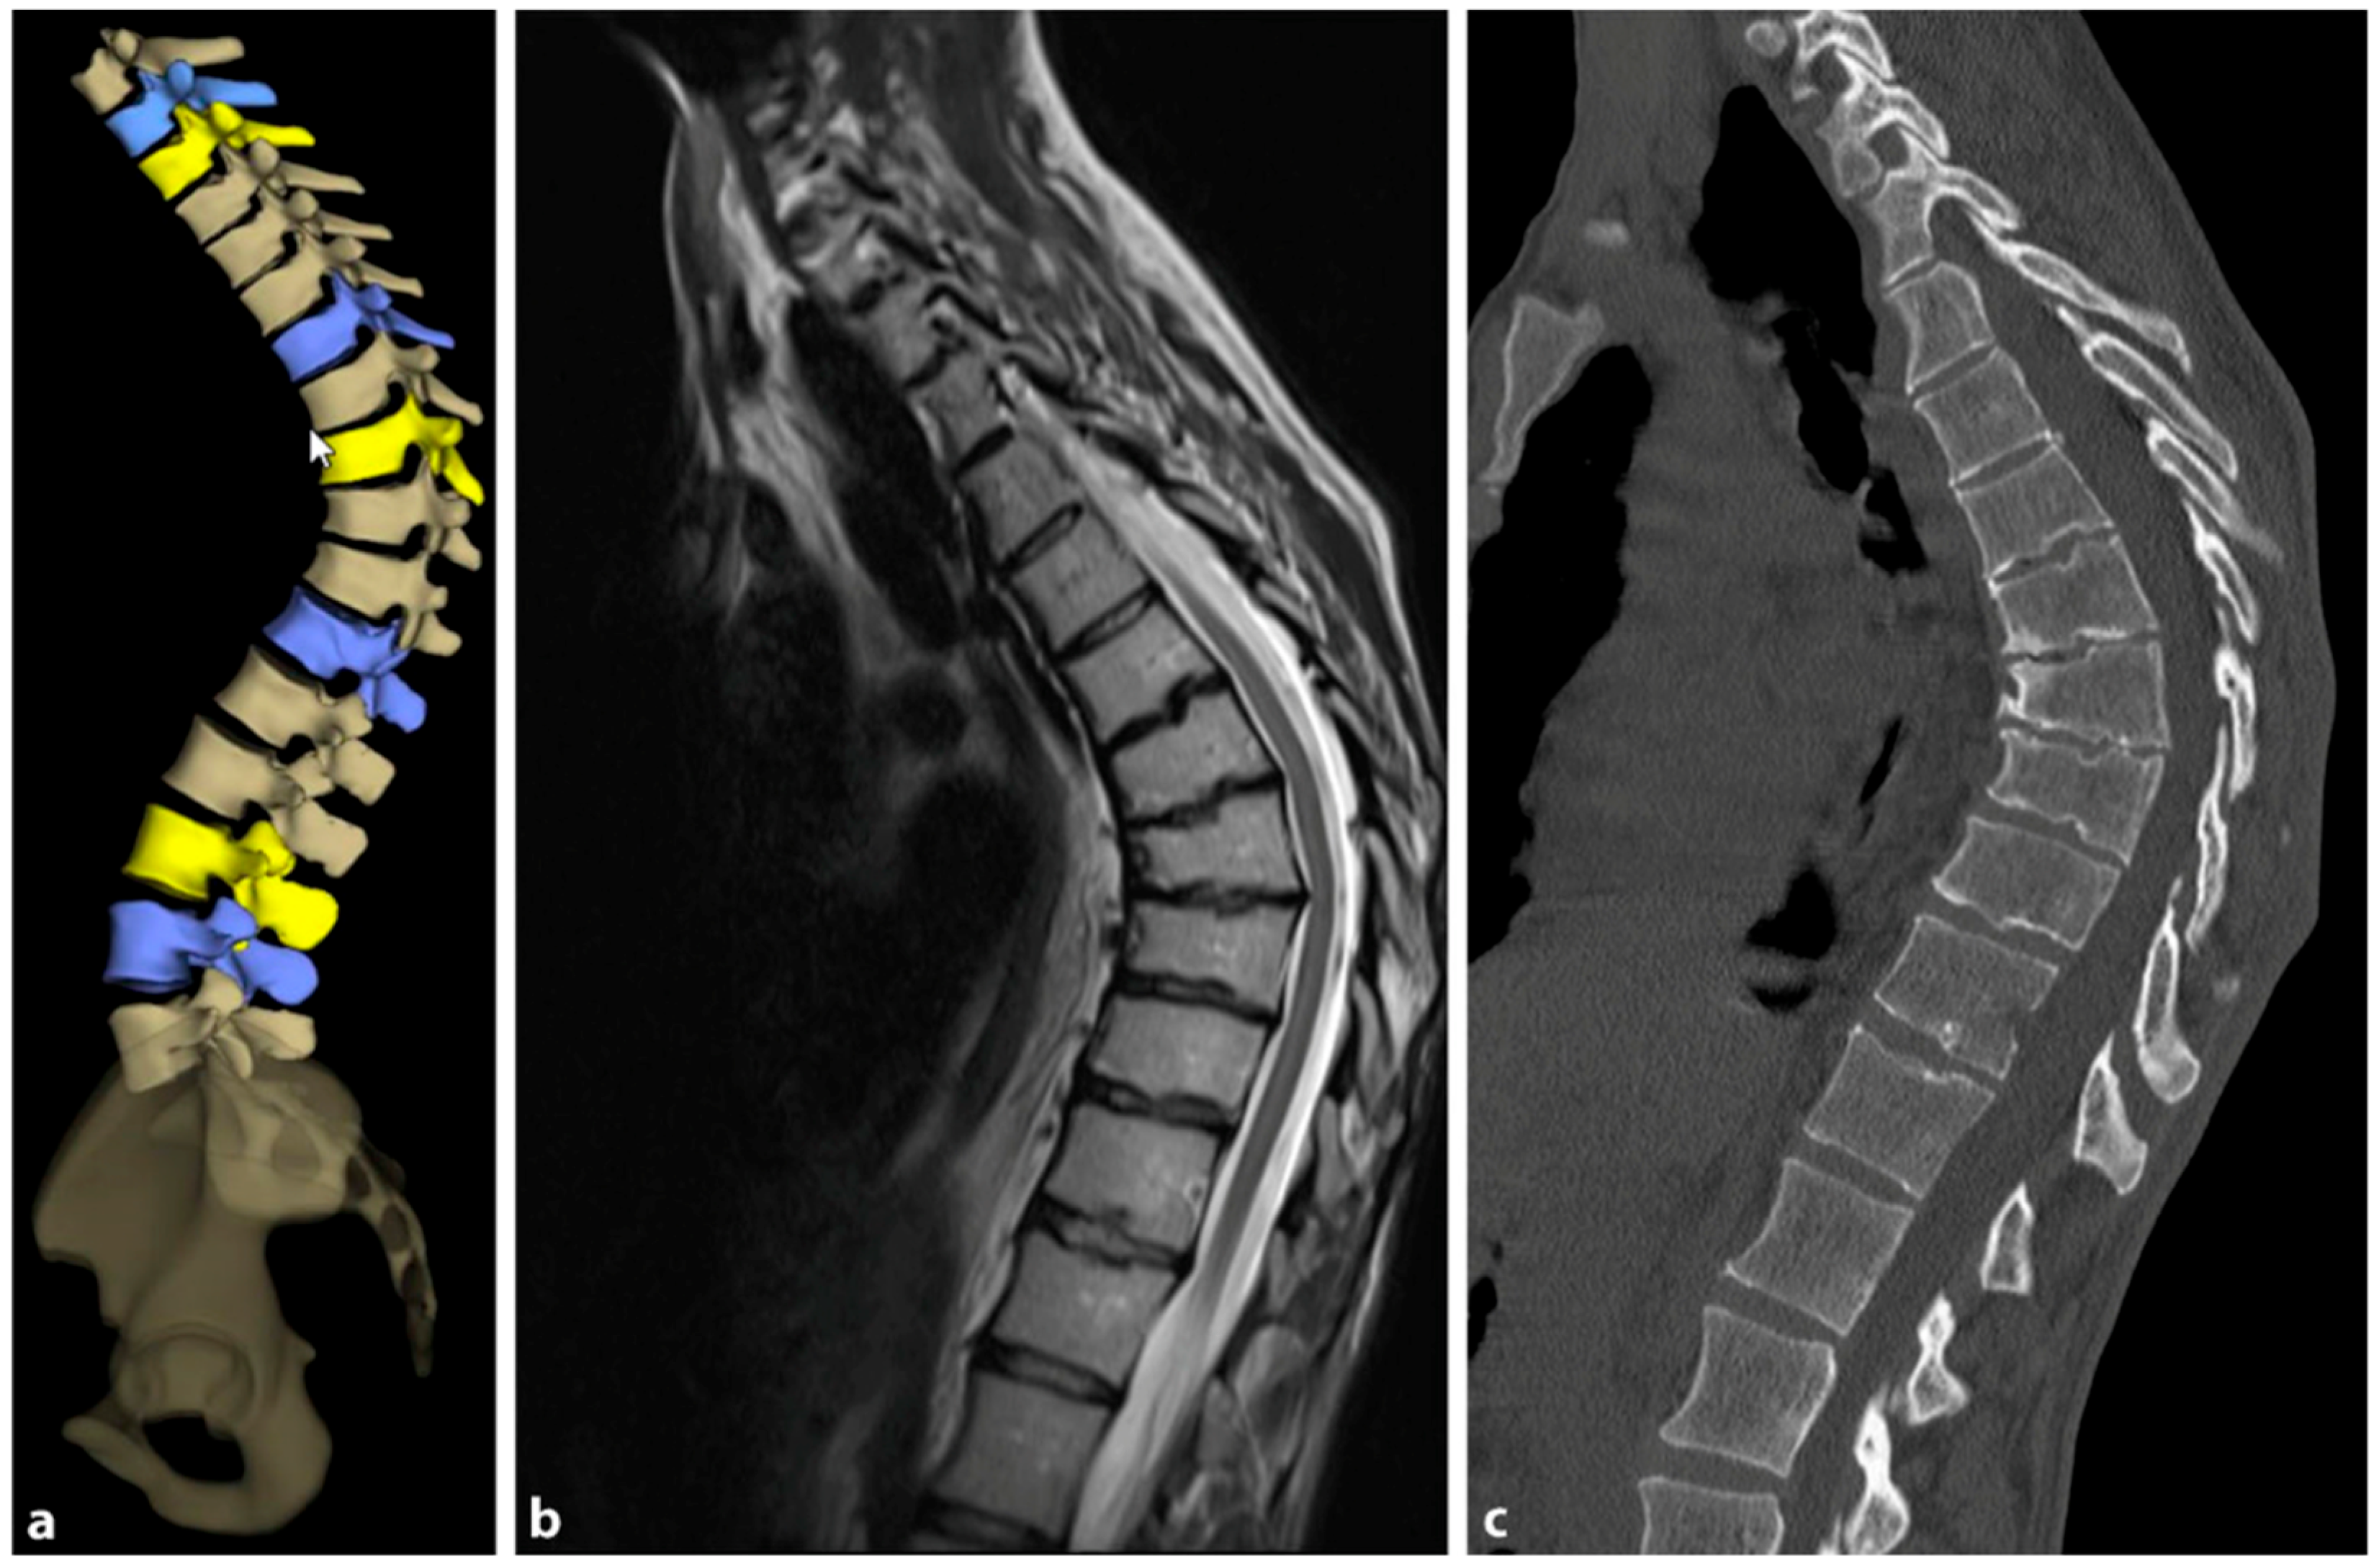

4.2.2. Magnetic Resonance Imaging

The need for MRI diagnosis has been demonstrated in several studies. In a recent study, the prevalence of syringomyelia was found to be 5.8% in patients with SD [89]. MRI is an obligatory preoperative preparation to exclude myelon compression, thoracic disc herniation, or spinal canal stenosis. Figure 9 provides a comparative visualization of thoracic SD captured through different imaging techniques: stereoradiography, MRI, and computer tomography (CT).